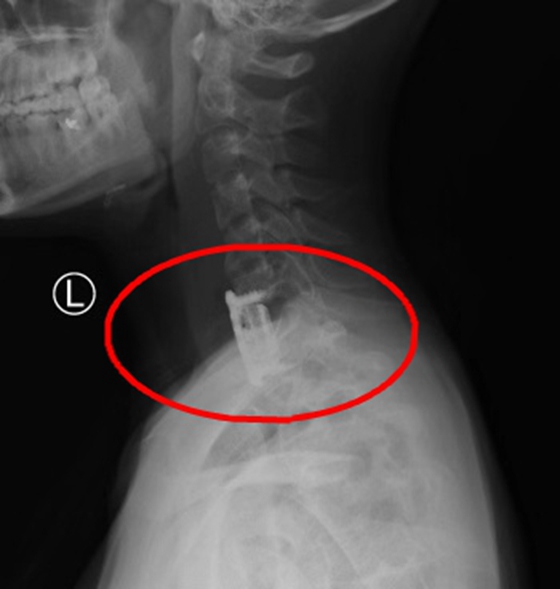

人工椎体置换术后

12月17日,张朝跃教授、张丕胜主任医师及陈芳田副主任医师组成的手术团队为患者实施了颈椎前路病灶清除人工椎体置换手术。术后,患者痛苦立马解除,经过骨科医师及金惠护士长带领的护理团队悉心照料和康复指导,目前已经在头颈胸支具保护下顺利恢复中。

据悉,人工椎体置换能即刻恢复脊柱序列,有效重建脊柱稳定性,又可清除病灶防止复发,并能将有效药物置入其中,尤其适用于脊柱结核、感染或肿瘤骨质破坏严重患者,该项手术在常德地区的首次开展标志了我院骨科的又一领先突破,更是让常德乃至湘西北地区患者能就近享受优质医疗资源的有力证明。